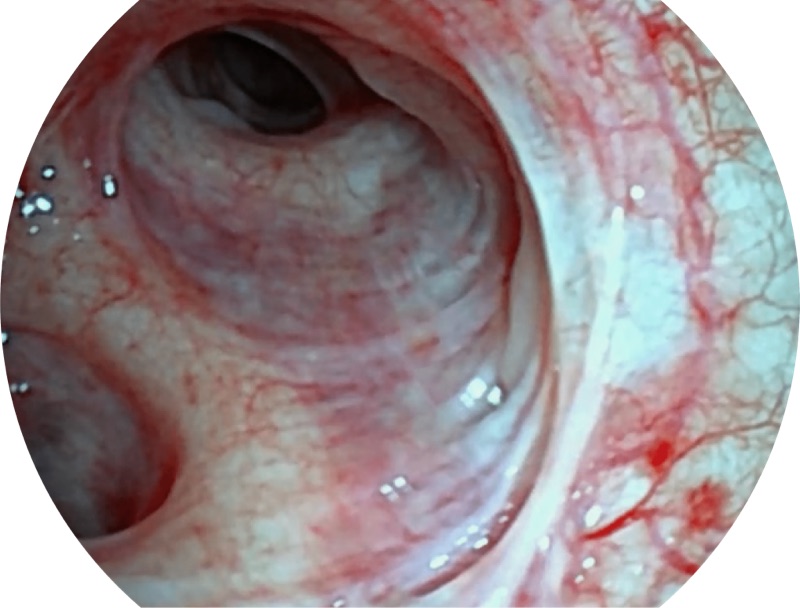

白光